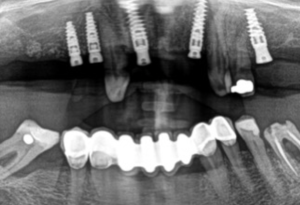

- Radiographic Analysis: Panoramic and periapical radiographs to evaluate bone quality and quantity for implants.

- Implant Planning:

Using radiographs or CBCT scans, the number and position of implants are planned to optimize support for the final prosthesis. - Surgical Procedure:

Implants are placed into the anterior maxilla under sterile conditions, ensuring primary stability. - Healing Phase: